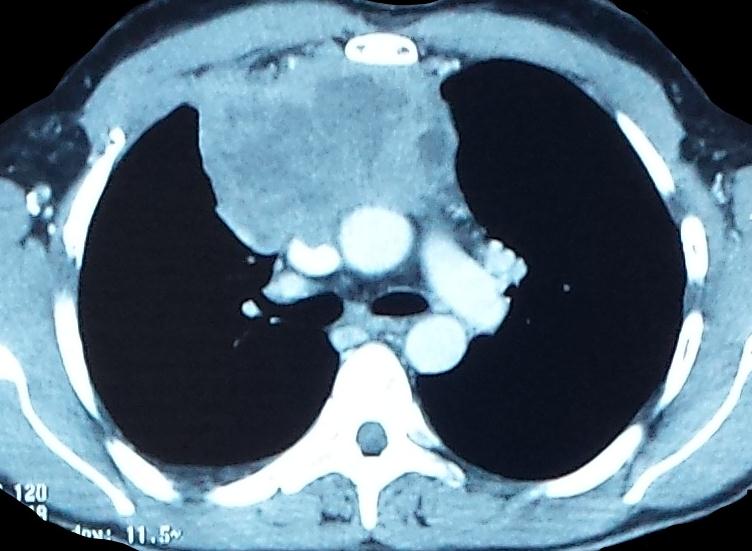

Face Chest x-ray had highlighted right anterior Mediastinal opacity with right low abundance pleural effusion (Figure 1). On a chest CT scan with contrast injection, the mass was tissue, heterogeneous, and measured 73x93x108mm. This mass included the superior vena cava and right innominated venous trunk that was the seat of intraluminal thrombosis associated with mediastinal lymph nodes (Figure 2).

Figure 2: Chest CT scan showing a right antero-posterior mediastinal mass, tissue, heterogeneous, contact with the Mediastinal vascular structures, without obvious wall extension |